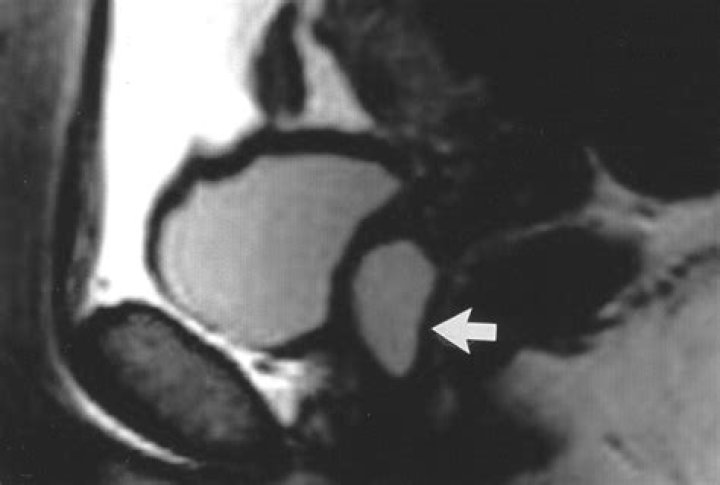

Paraurethral Cyst Paraurethral cysts, also known as Skene’s glands, are found in the wall of the vagina near the urethra. In a newborn, Skene’s duct can become blocked by a large cyst filled with hormone secretions. Sometimes the cyst may close off the urethral opening.

What is Parameatal cyst?

A parameatal cyst is a benign, usually asymptomatic condition that may contain a variety of epithelial types. A physical examination is sufficient to make a diagnosis and a complete surgical excision is necessary to obtain good cosmetic results without recurrence.